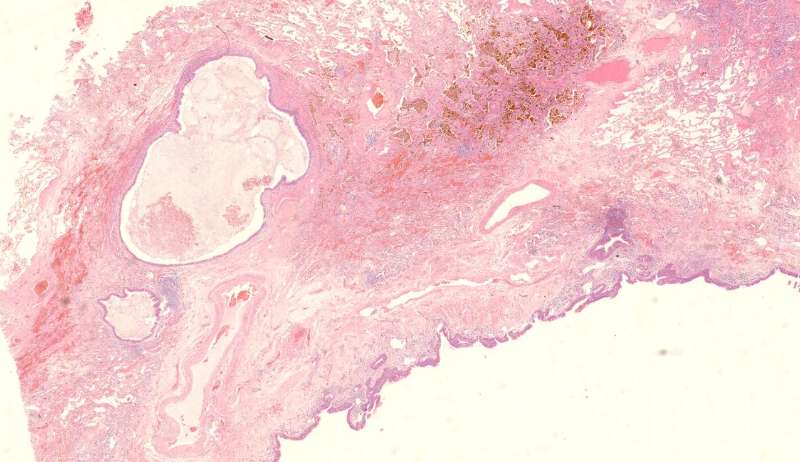

这个人的支气管腔有一大团曲霉,被冲掉了,扩张的支气管有炎症细胞浸润,还有支气管外侧,含铁血黄素沉积。

为什么有含铁血黄素呢? 曲霉菌容易使周围出现出血。太多含铁血黄素,吞不完 剩下一点曲霉菌,看看:

刚才的曲霉菌是这里?王:是的,这里有残留菌丝 第二例曲霉

曲霉菌孢子很少见到,基本都是菌丝团,这里也是支气管扩张区,菌丝团偏黄褐色,也快死了。